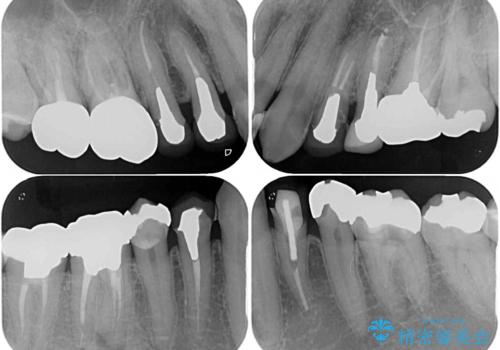

- 飛び出している上顎前歯と、奥歯に多くある銀歯を気にして来院された患者様です。

矯正治療後には、奥歯の銀歯をすべてセラミックにて補綴治療することとしました。

補綴治療にあたり、痛みのある歯に対して根管治療を行うこととしましたが、処置が必要な歯が多かったため、期間を要しました。